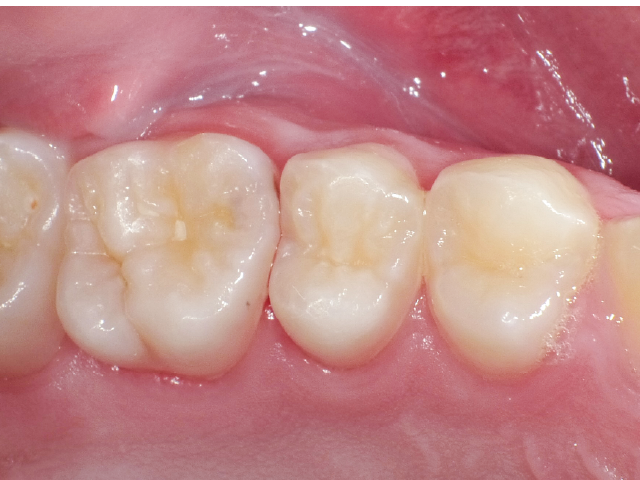

②充填段階(図10~22)

窩洞形成完了後は隣接面部健全歯質の残存範囲によりコンポジットレジンの充填時に用いるマトリックスシステムを選択していきますが、今回はシンプルな操作で設置可能なトッフルマイヤータイプのマトリックスシステムを選びました。隣在歯との距離が小さく、フラットな隣接面形態の再現が必要な症例には最適で、同時に精度の高い窩洞の防湿も可能です。使用したメタルのマトリックスバンドの厚さは30µmと非常に薄く、隣在歯との間に適切な接触関係を回復することができます。

接着操作には窩縁部エナメル質へのセレクティブエッチングに続いて、2ステップタイプのセルフエッチングシステム(クリアフィル® メガボンド®2 : クラレノリタケデンタル)を使用し、フロアブルレジンとペーストタイプレジンとを併用したシンプルな積層充填操作により隣接面形態を回復しました。